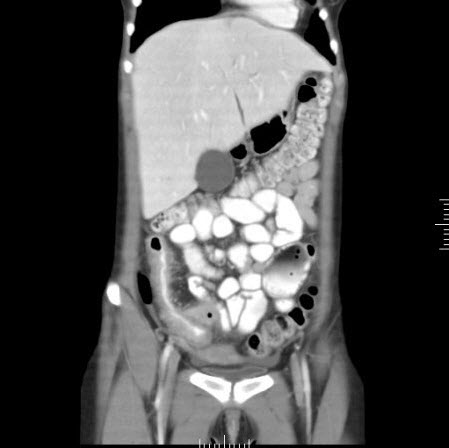

Abscesso hepático: tomografia computadorizada (TC) (vista coronal) mostrando abscesso hepático em um homem de 46 anos de idade que apresentava febre, fadiga e tosse

Do acervo de imagens radiológicas do Massachusetts General Hospital